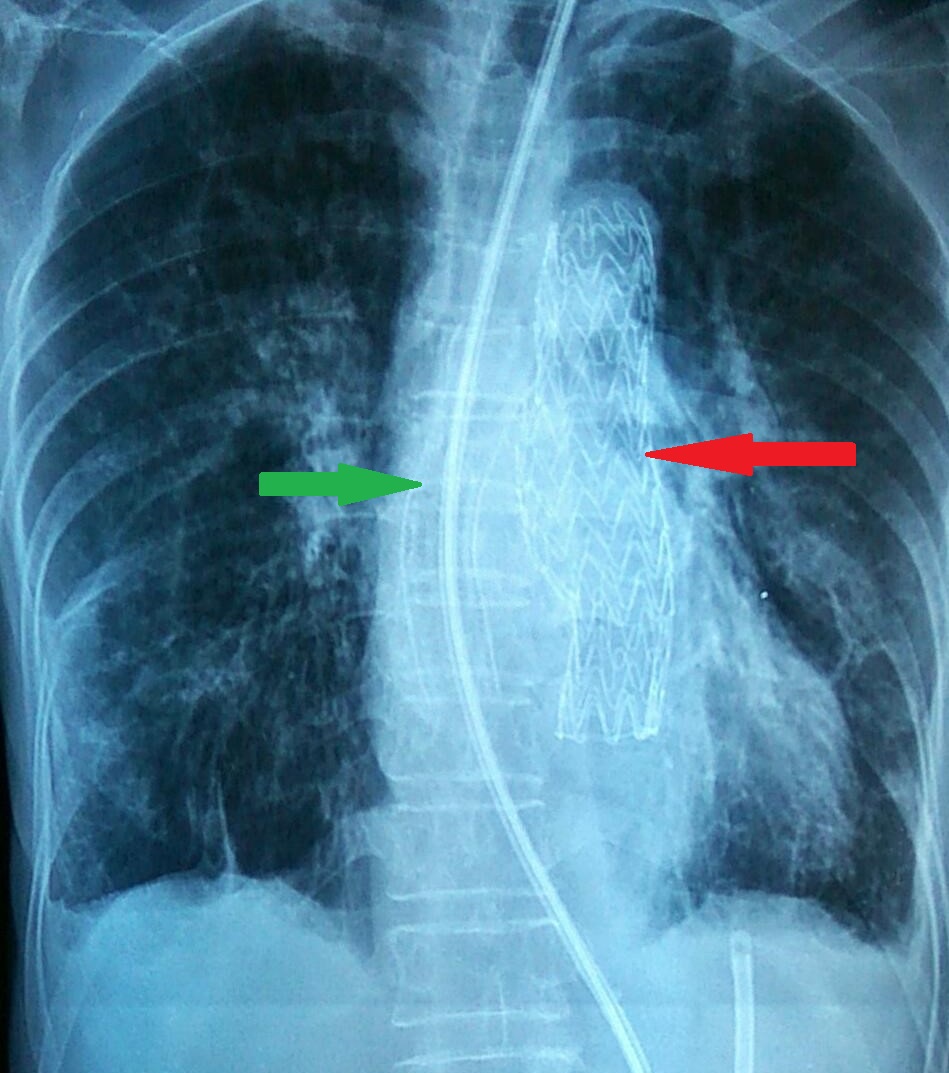

Οισοφαγικό (πράσινο βέλος) και θωρακικής αορτής (κόκκινο βέλος) stent σε θέση (Ευγενική παραχώρηση Dr. V. Penopoulos)